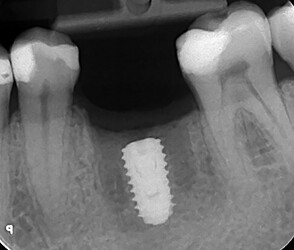

Ossification is a complex and sometimes unpredictable process. I think 10 weeks is a too soon for implant placement since the extraction socket hasn’t fully calcified and you still have spongy bone inside the socket and psuedoperiosteum on the occlusal of the socket. I noticed radiographically i can see still see the socket. I usually enter and place implant at 4 months minimum post extraction, ideally 6 months, when radiographically the socket is mostly radiopaque indicating more calcification and ridge remodeled consistent to final dimensions.

I also noticed at implant placement i see 2 occlusal defects mesial and distal of the implant (most likely indicating mesial and distal root of previously extraction). which indicated the ridge is not fully ossified or calcified. i wonder if during osteotomy you felt soft bone instead of the usually hard mandibular bone. i think at implant placement you should have grafted. the occlusal is kind of flat, as if you did some occlusal reduction of some kind.

Your implant position is impeccable. good depth and orientation in the ridge.